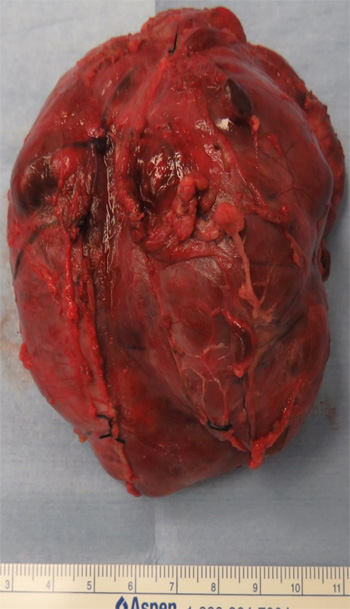

腫瘍摘出術

・手術時間 13時間5分

・手術時間 13時間5分

・出 血 100ml

・腫 瘍 6cm×8cm×9cm 156g

血管はすべて温存した状態で腫瘍を 摘出することができた